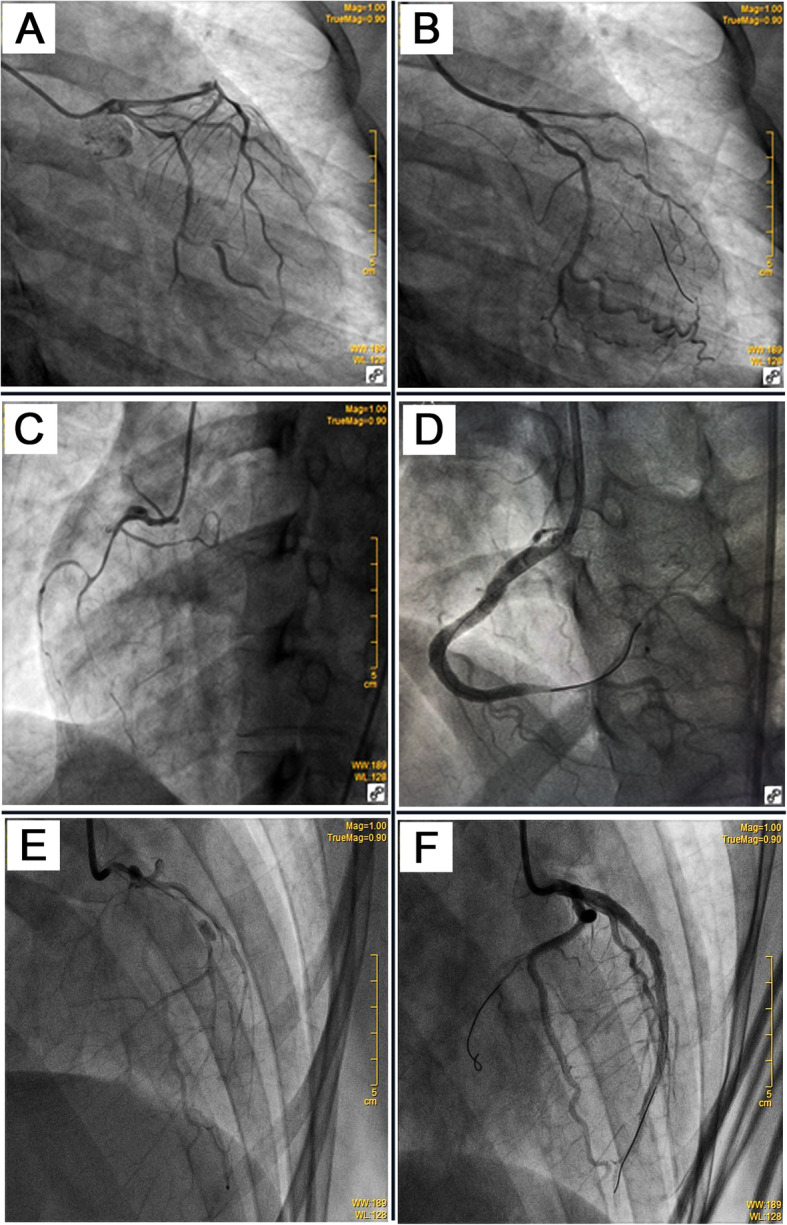

Fig. 2.

a Left coronary angiogram showed long diffuse stenosis in LAD and LCX. b The TIMI 3 flow was restored in distal LAD after dilatation with undersized balloons at low-pressure. c Three days after the initial PCI, the MI recurred in this patient. The angiography showed coronary dissection in the ostium of the right coronary artery with TIMI1 flow 1. d No residual stenosis was achieved after implantation with multiple drug-eluting stents from distal to proximal segments of the right coronary artery. e Three days later, the patient suffered from MI again. Coronary angiogram demonstrated long diffuse stenosis in LAD and LCX with TIMI flow 3. f Multiple drug-eluting stents were implanted into focal lesions of LAD, LCX, and LMC arteries to seal intimal tears and achieve the optimal results of no residual stenosis and restoration of TIMI 3 flow. LAD: left anterior descending coronary artery; LCX: left circumflex coronary artery; LMC: left main coronary artery; TIMI: Thrombolysis in Myocardial Infarction